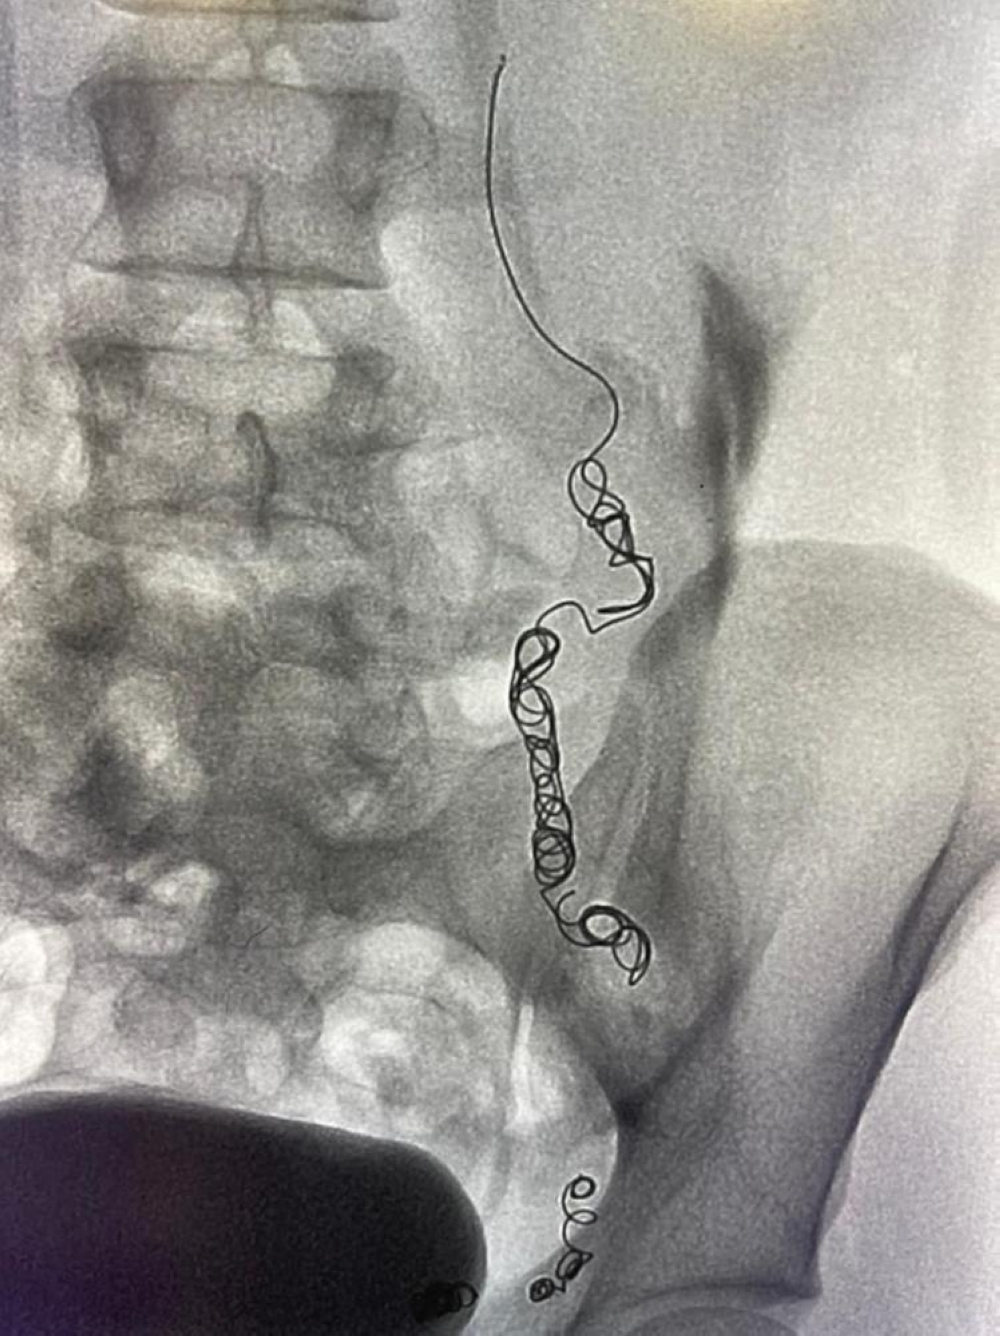

وقام الفريق الطبي بقيادة د.محمد شراحيلي استشاري الأشعة التداخلية، باستخدام القسطرة الوريدية حيث تم تحديد واستكشاف جميع الأوردة المسببة لارتجاع الدوالي مرة أخرى، موضحا علاجها بطريقة اللفائف المعدنية الدقيقة وحقن المادة المتصلبة.

وأضاف:" تساعد تقنيات الأشعة التداخلية باستخدام القسطرة تحت استرشاد الأشعة الصوتية والفلورية من أحدث الطرق العلاجية لدوالي الخصية حيث يتوفر العديد من تقنيات العلاج و منها إغلاق الوريد المتسبب في الدوالي باستخدام اللفائف المعدنية الدقيقة أو من خلال حقن مادة صمغية أو متصلبة، حيث يتم الوصول لتلك الأوردة من خلال فتحة دقيقة بالجلد لذراع المريض لا تتجاوز الـ 2 ملم و لا تترك علامات جراحية على الجلد" .